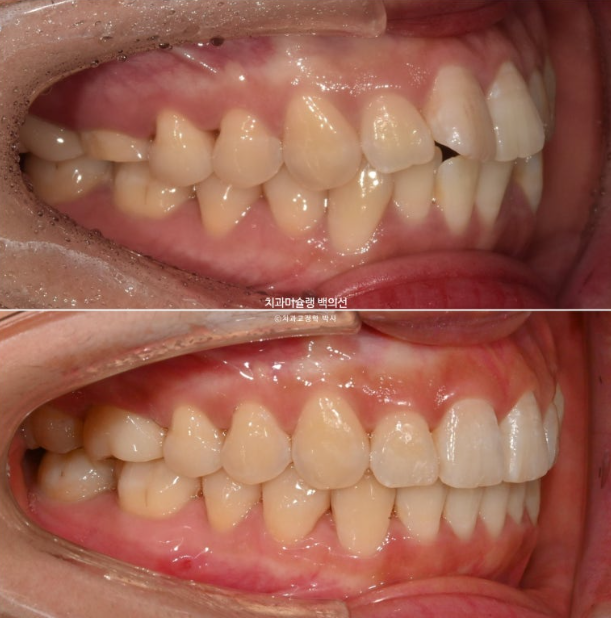

쓰러졌던 큰어금니들은 잘 섰으나 한쪽 어금니 교합의 개선이 좀 더 필요합니다.

25년 5월부터 8월까지 14개 추가장치를 모두 낀 후 치료를 마무리 했습니다.

중심선은 일치하고 교합도 좋습니다.

발치된 큰어금니 자리를 뒤에있는 제2대구치와 사랑니로 감쪽같이 대체되었습니다.

23.10~25.08